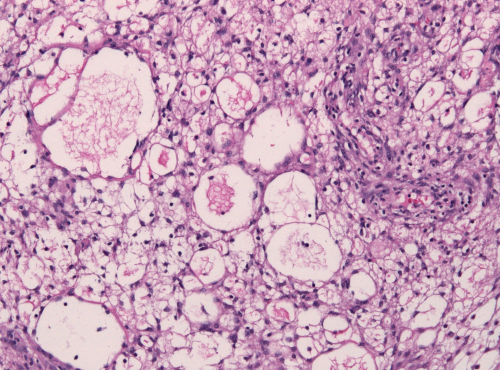

脑膜瘤治疗好方法

脑膜瘤 是发生在脑膜上的脑瘤,脑膜是包围和保护大脑和脊髓的组织(图1)。尽管大多数脑膜瘤不是癌性的,但当它们生长并压迫大脑或脊髓的重要部位时,会造成问题。脑膜瘤的病因尚...